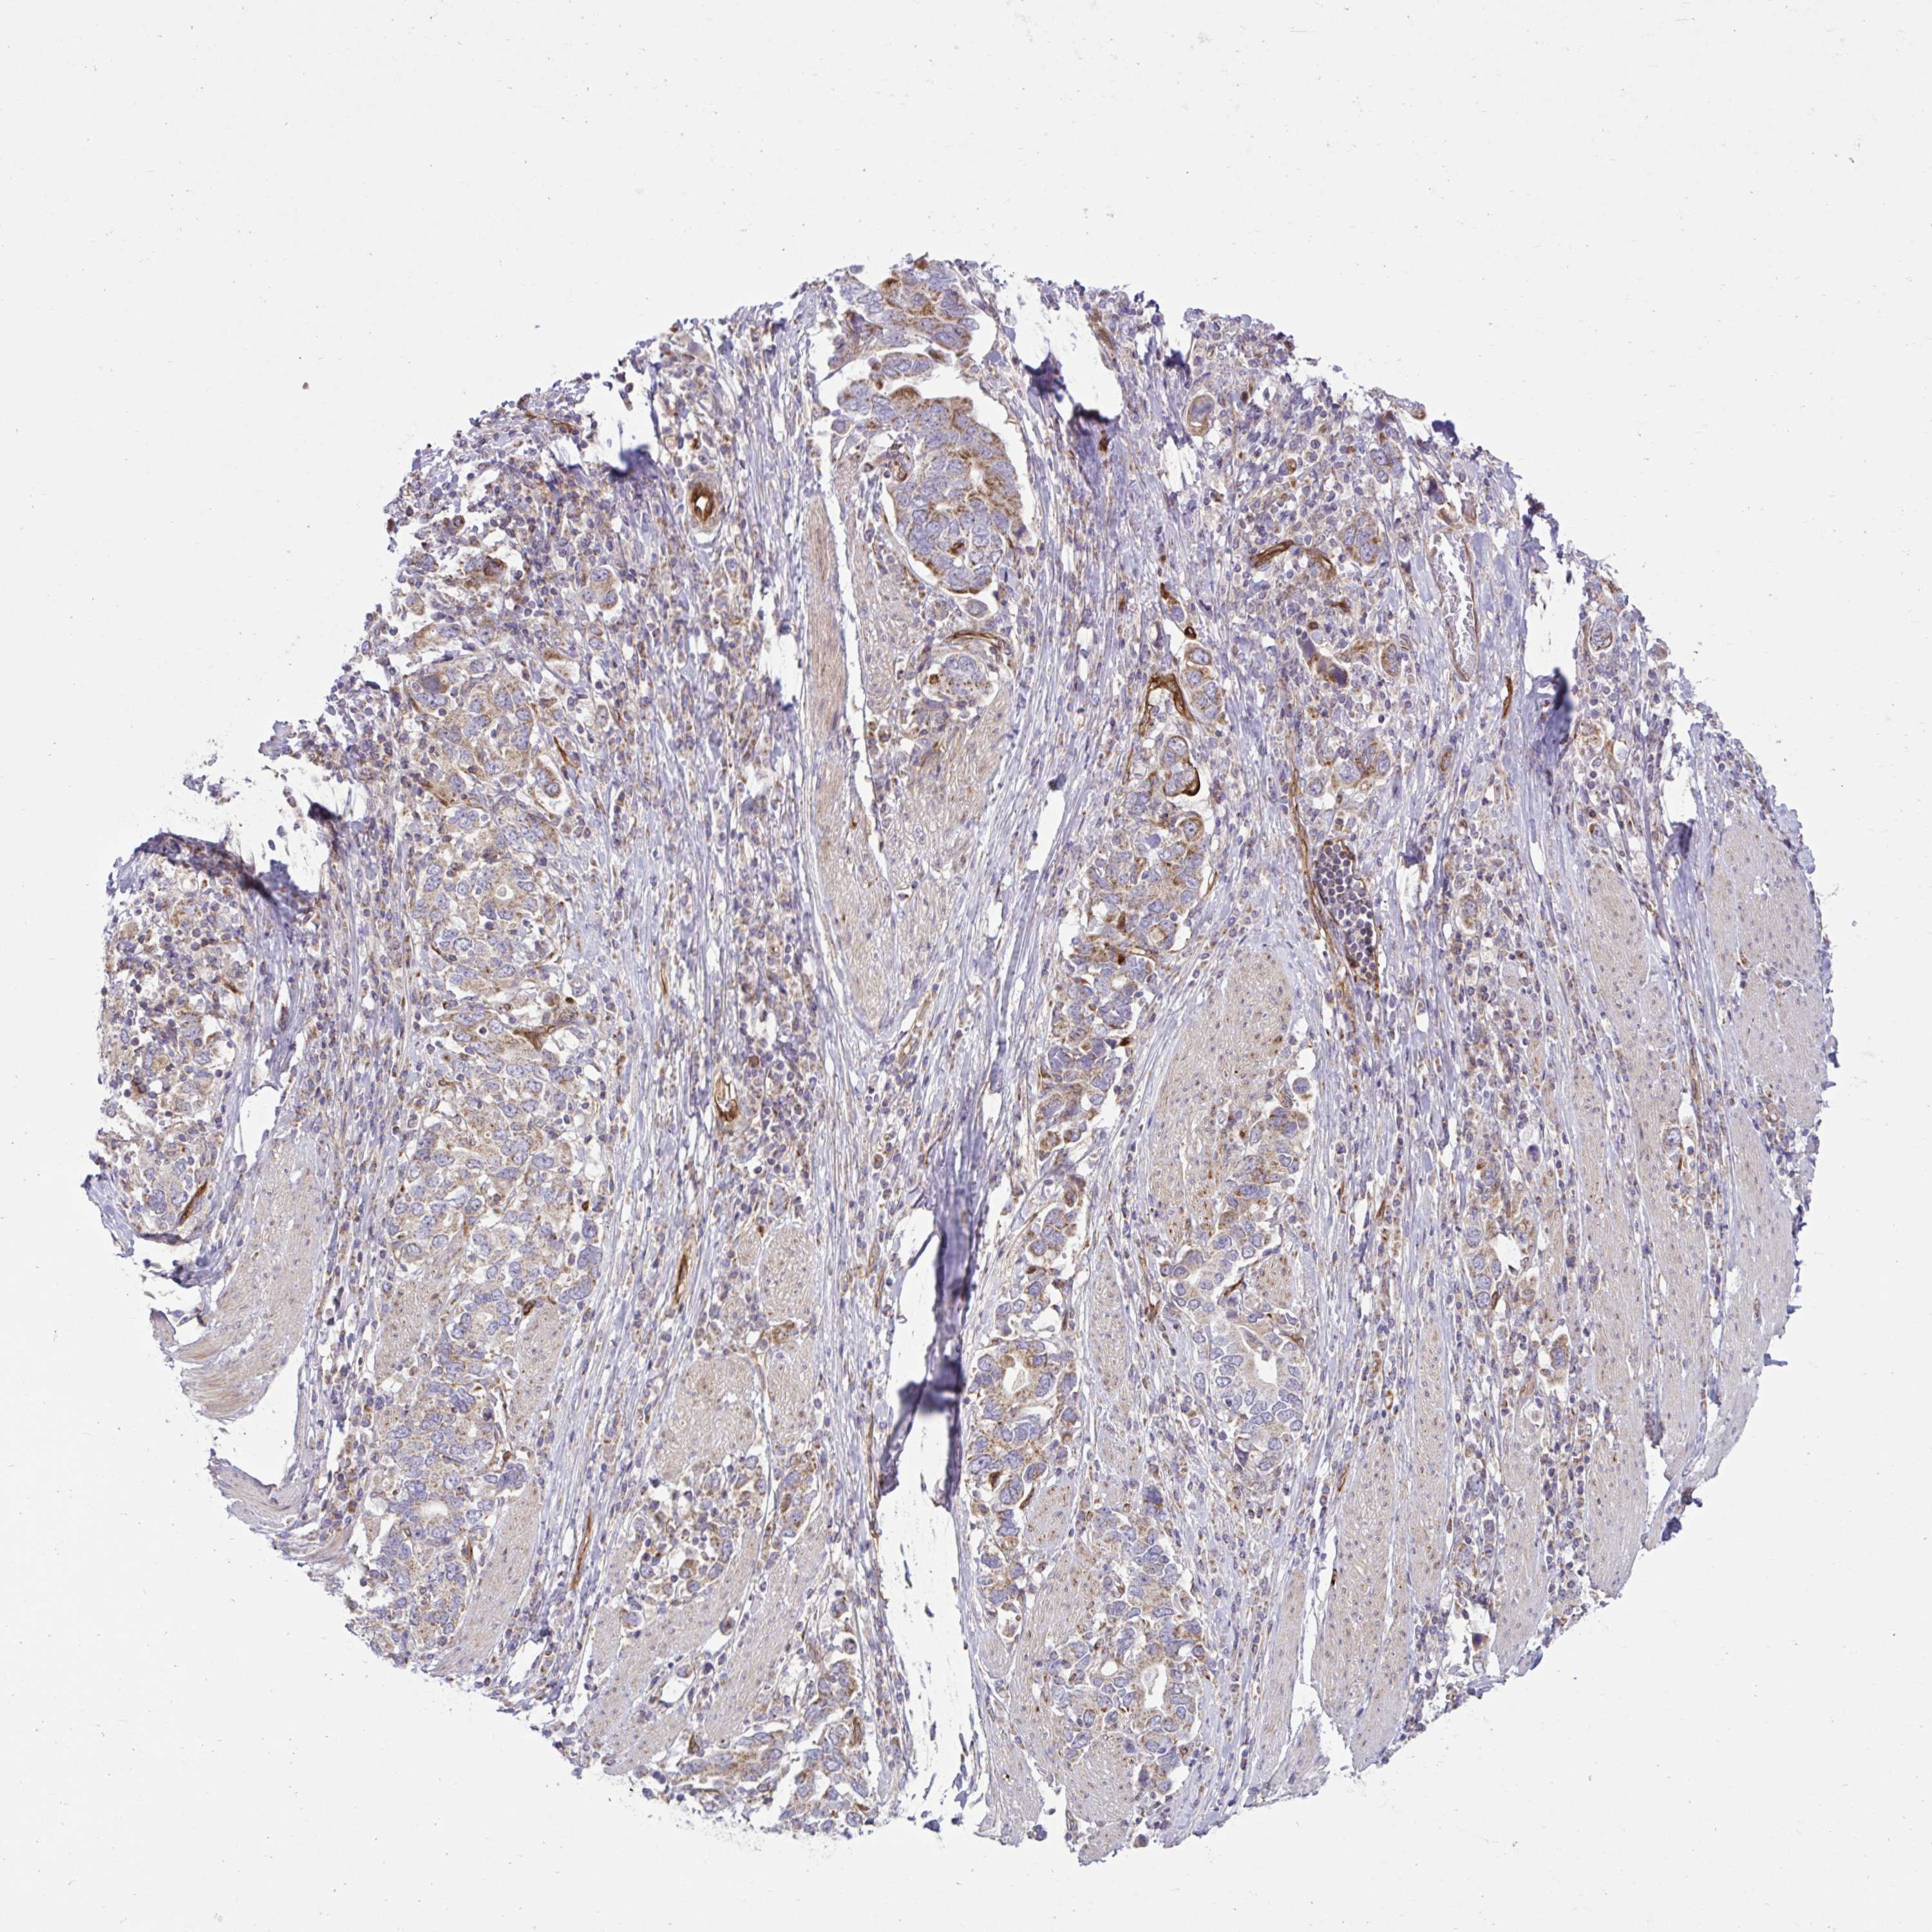

STOMACH CANCER - Protein expressioni

A mouse-over function shows sample information and annotation data. Click on an image to view it in a full screen mode. Samples can be filtered based on level of antibody staining by selecting one or several of the following categories: high, medium, low and not detected. The assay and annotation is described here.

Note that samples used for immunohistochemistry by the Human Protein Atlas do not correspond to samples in the TCGA dataset.

Antibody stainingi

Antibody staining in the annotated cell types in the current human tissue is reported as not detected, low, medium, or high, based on conventional immunohistochemistry profiling in selected tissues. This score is based on the combination of the staining intensity and fraction of stained cells.

Each image is clickable and will lead to virtual microscopy that enables deeper exploration of all samples and also displays staining intensity scores, fraction scores and subcellular localization as well as patient and tissue information for each sample.

Antibody HPA058455

Staining

High

Medium

Low

Not detected

Intensity

Strong

Moderate

Weak

Negative

Quantity

>75%

75%-25%

<25%

None

Location

Nuclear

Cytoplasmic/membranous

Cytoplasmic/membranous,nuclear

Adenocarcinoma, NOS